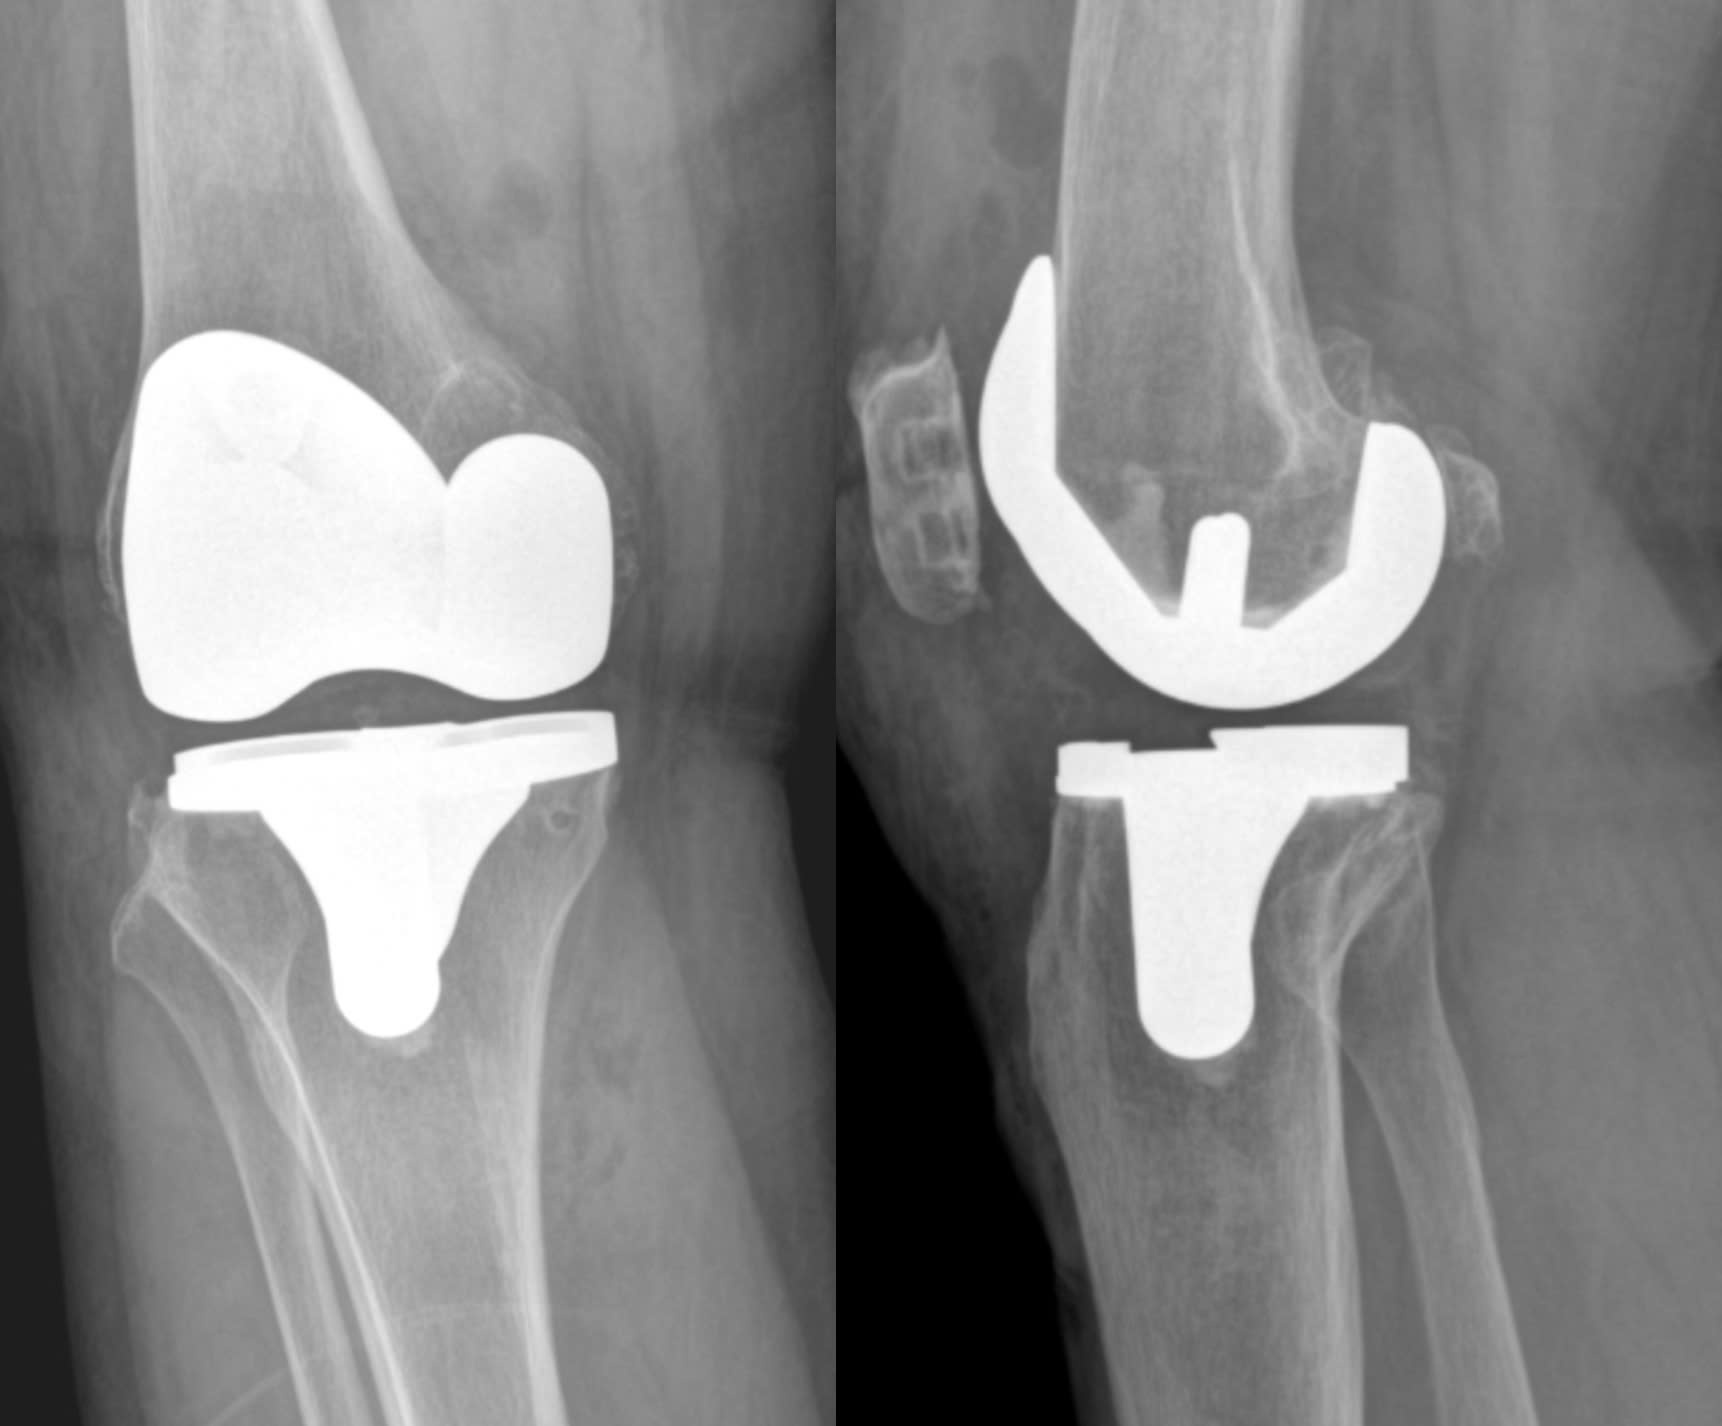

X-ray of Mrs. Ngan's artificial knee joint. Photo: *Tam Anh General Hospital*

Dr. Quyen diagnosed Mrs. Ngan with stage 4 osteoarthritis in both knees, with complete loss of cartilage and numerous bone spurs around the joints, reducing range of motion and causing joint deformity. He recommended total knee replacement surgery. To minimize the risk of complications in older patients, the doctor planned staged surgeries, starting with the right knee, with the left knee scheduled for surgery 3 months later. The patient was prescribed anti-inflammatory and nerve pain medication before surgery to help manage post-operative pain.

Mrs. Ngan received spinal anesthesia and mild sedation to stabilize hemodynamics and minimize blood loss. Dr. Quyen used a subvastus approach, fully preserving the patient's muscle. The cartilage lost due to osteoarthritis was replaced with an artificial knee joint. She also received intra-articular injections for pain control, a safe method that doesn't cause muscle weakness and provides effective pain relief for up to 12 hours post-surgery. As a result, she began in-bed exercises just two hours after surgery, started walking after 6 hours, and was discharged after two days.

Two months later, Mrs. Ngan underwent surgery on her remaining knee. This time, the procedure was further optimized, resulting in less blood loss, less soft tissue damage, and reduced pain. She recovered more quickly and efficiently. 4 hours after the second surgery, she began walking with her two new knee joints and was discharged just 24 hours after the knee replacement surgery.